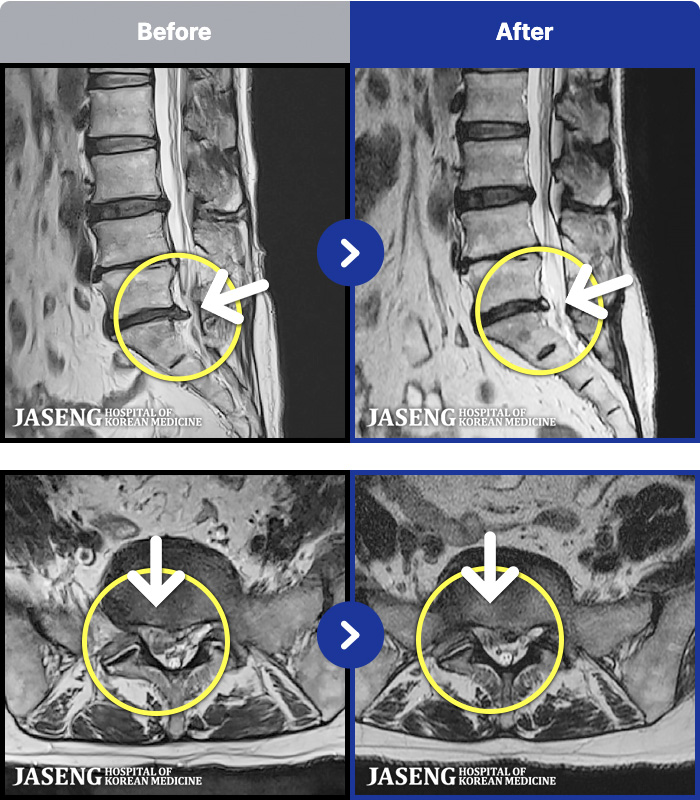

57 MRI ũ ʸ Ȯϼ.

MRI ġ

Ƹ ϰ ־.

[õ] 25.03.18~25.07.22

ȯںп Ǹ ǿ ԿǾ, ο ġ ۿ Ƿ ġḦ Ͻñ ٶϴ.

[õ_㸮ũ] Ƹ ϰ ־.